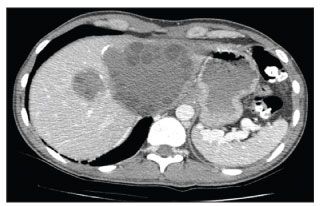

Figure 1 – A contrast CT scan of the abdomen demonstrates a large echinococcal cyst with multiple daughter cysts occupying most of the left lobe of the liver and a smaller cyst in the right dome of the liver.

He was afebrile, and findings from his physical examination were remarkable only for a well-healed posterior thoracic scar on the left side and tender hepatomegaly. Laboratory tests revealed a white blood cell count of 8500/µL, with a total eosinophil count of 510/µL; normal electrolyte, bilirubin, and aspartate aminotransferase levels; and a mildly elevated alanine aminotransferase level. Results of a serum antibody test for E granulosus were positive. The chest radiographic findings were normal. A CT scan (Figure 1) and an ultrasonogram (Figure 2) of the abdomen demonstrated multiple daughter cysts in both the left and right lobes of the liver. Magnetic resonance angiography (MRA) of the chest showed multiple intraluminal echinococcal cysts in the right pulmonary artery extending to apical branches of the right upper lobe pulmonary artery (Figure 3).